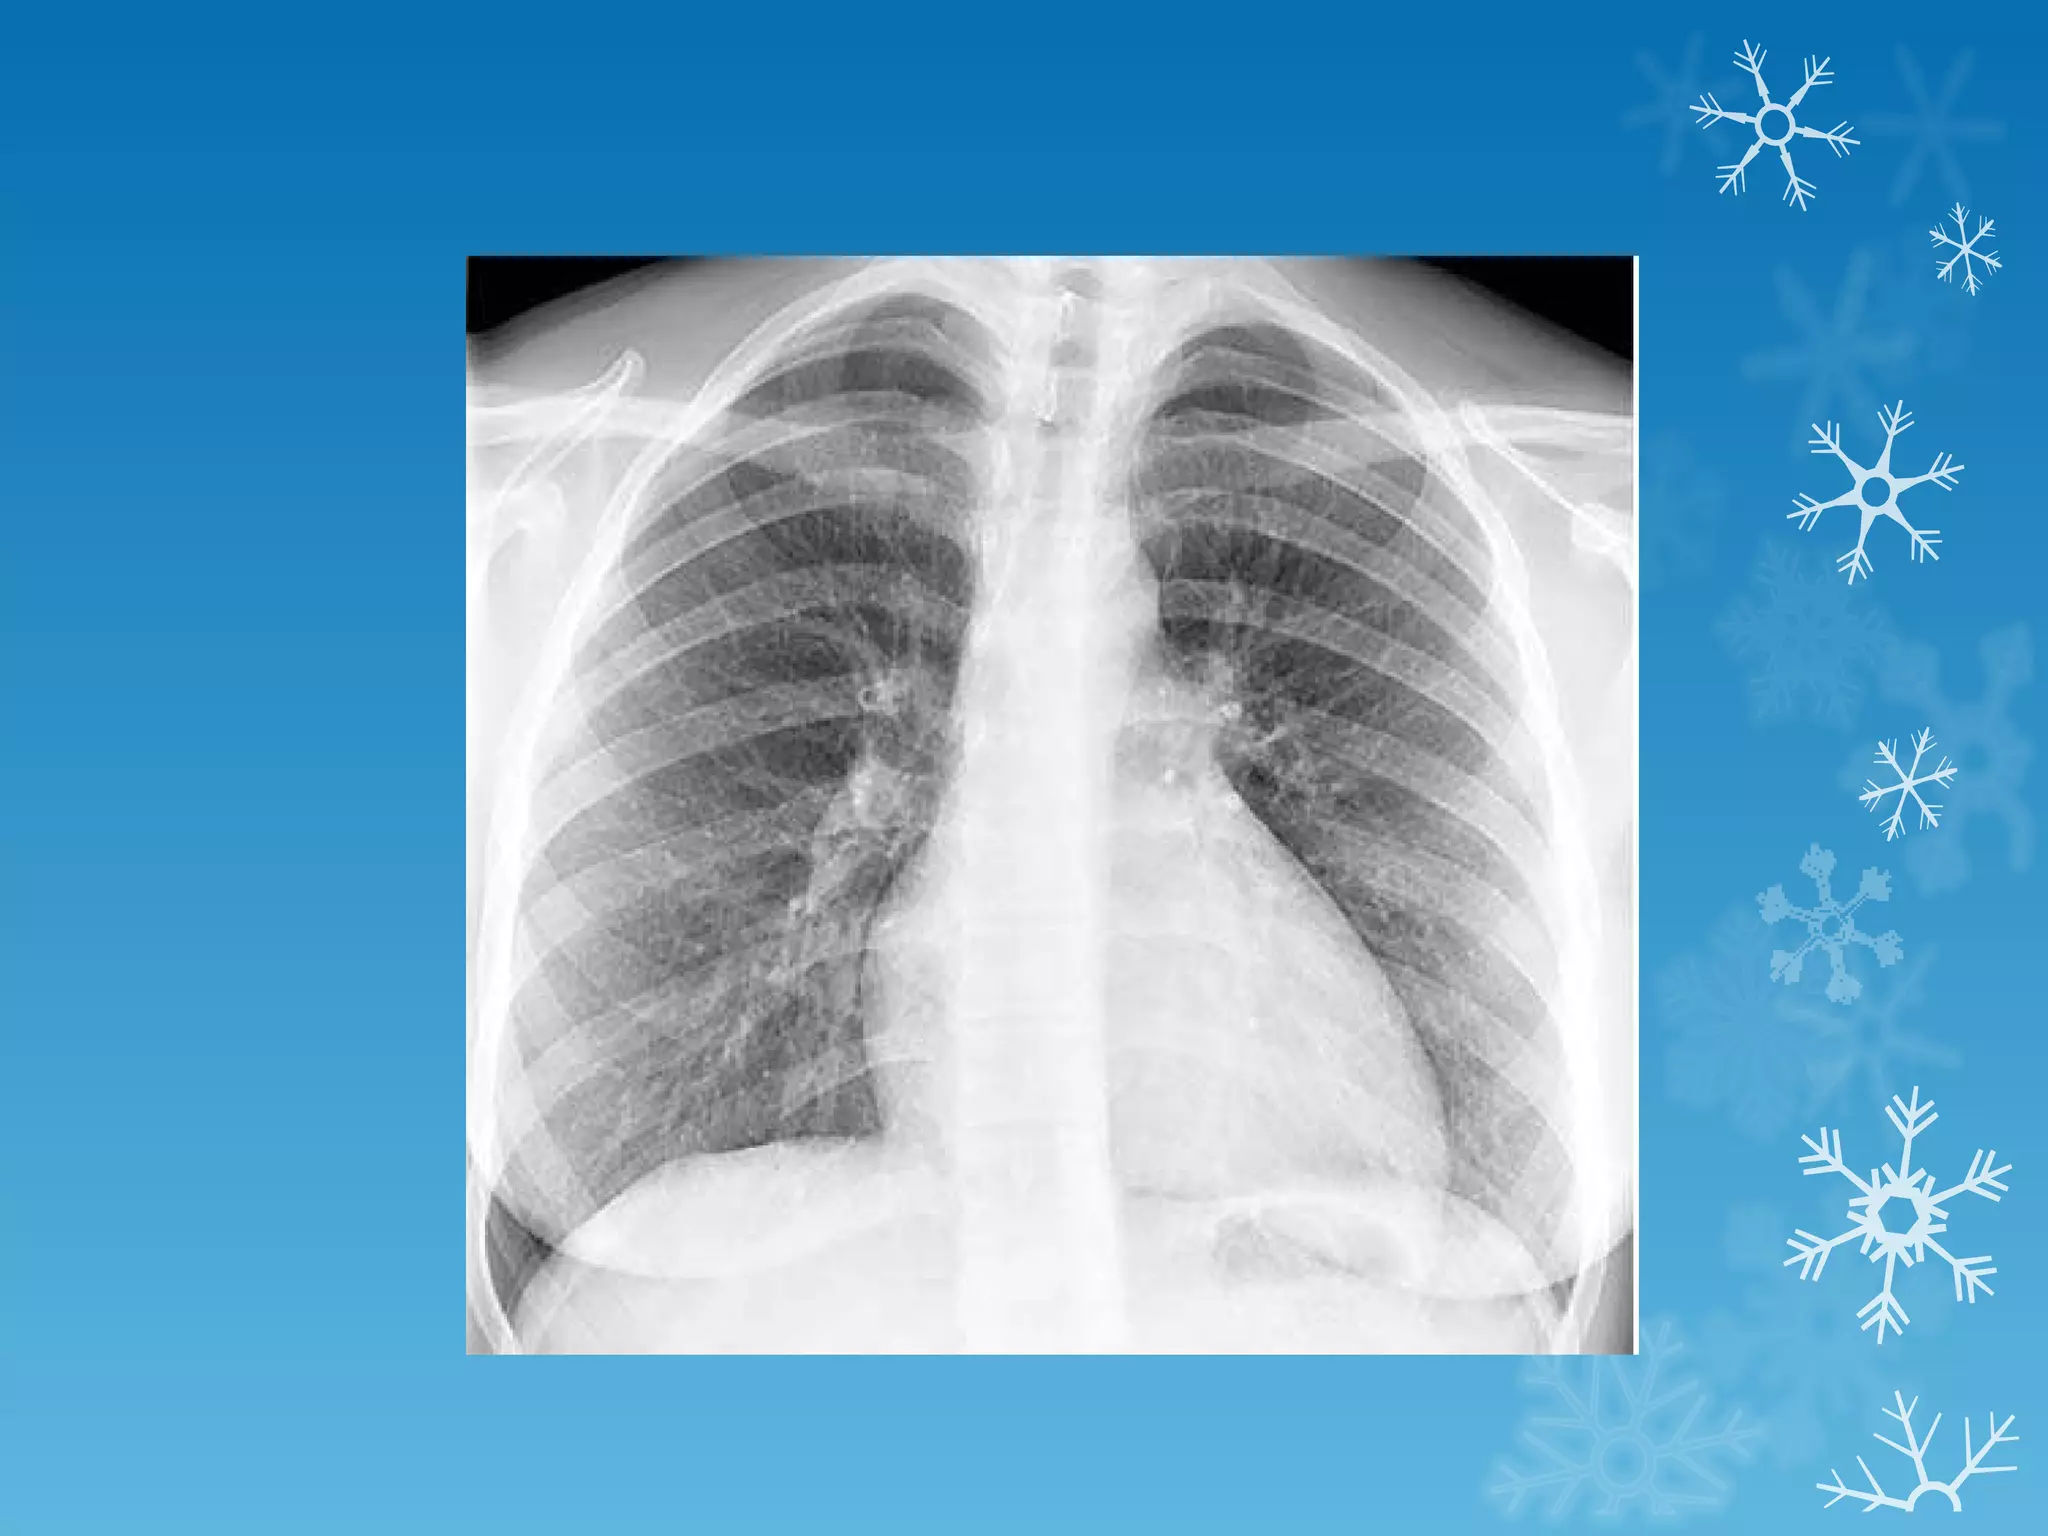

This document discusses chest x-ray interpretation and provides guidance on evaluating x-rays. It explains that tissue density determines how an x-ray beam penetrates, with denser tissues appearing whiter and less dense tissues appearing blacker. It also outlines different chest x-ray views and factors to consider like patient orientation, age, gender, and rotation. Abnormalities are described as appearing too white, too black, too large, or in the wrong place. The document stresses a systematic approach of identifying, localizing, describing lesions, and providing differential diagnoses.